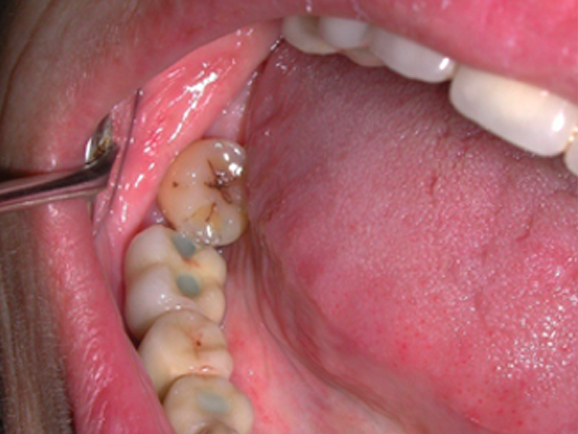

GLI ESITI

Rigenerazione ossea del pavimento del seno mascellare con incremento verticale di 12 mm ed orizzontale di 10 mm

Risultati estetici e funzionali conseguiti con la CHIRURGIA RIGENERATIVA